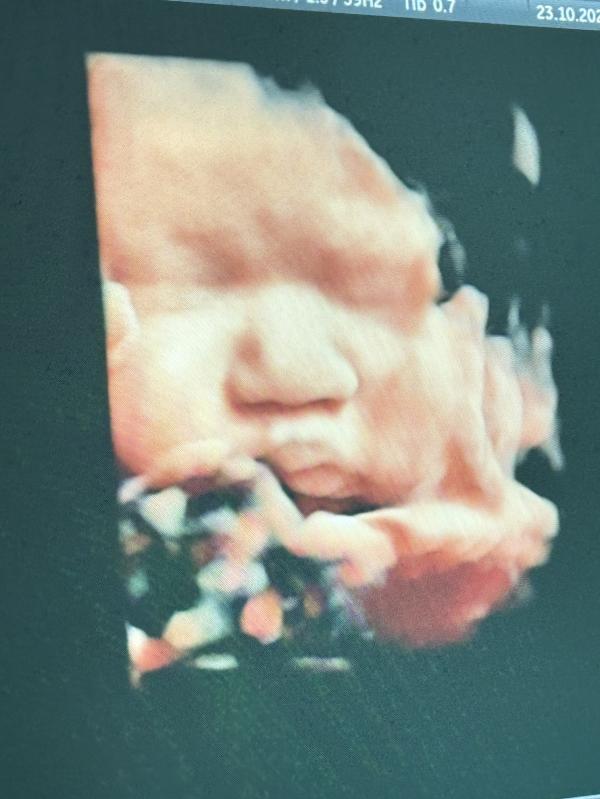

пиии, щечкина ✨🥰